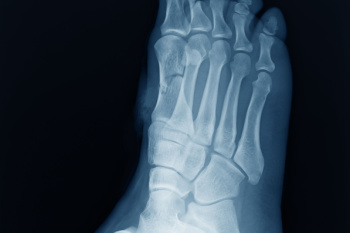

Due to the wide variety of potential causes of ankle pain, podiatrists will utilize a number of different methods to properly diagnose ankle pain. This can include asking for personal and family medical histories and of any recent injuries. Further diagnosis may include sensation tests, a physical examination, and potentially x-rays or other imaging tests.

Diagnosis

To figure out the cause of foot pain, podiatrists utilize several different methods. This can range from simple visual inspections and sensation tests to X-rays and MRI scans. Prior medical history, family medical history, and any recent physical traumatic events will all be taken into consideration for a proper diagnosis.

Diagnosis of cuboid syndrome is often difficult, and it is often misdiagnosed. X-rays, MRIs and CT scans often fail to properly show the cuboid subluxation. Although there isn’t a specific test used to diagnose cuboid syndrome, your podiatrist will usually check if pain is felt while pressing firmly on the cuboid bone of your foot.